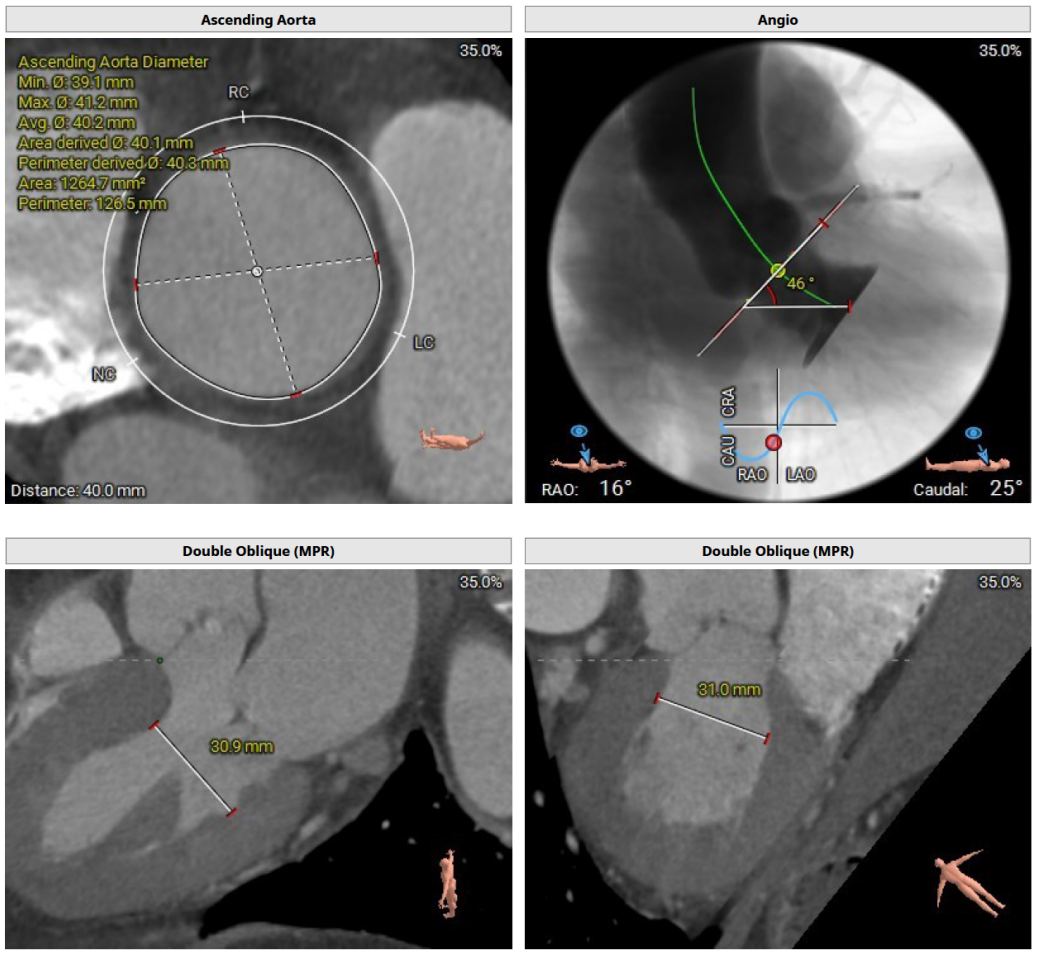

CT评估及手术策略

患者为三叶式主动脉瓣,重度反流。瓣叶交界轻度钙化。瓣环周长76.3 mm,平均径24.3 mm。LVOT周长77.3 mm,平均径24.0 mm。瓣上3.8 mm、5.0 mm、8.9 mm处空间为76.8 mm、82.8 mm、78.3 mm。STJ 周长105.7 mm,高度23 mm,升主周长126.5 mm 增宽、瓦氏窦大。综上所述建议TAV 27 瓣膜。左右冠高度15.6 mm、17.2 mm相对瓣膜支架可,冠脉风险低。股动脉入路血管轻度迂曲,双侧股动脉分叉高度可。腹主动脉、双侧髂总动脉散在钙化斑块。右侧股动脉平均内径最小6.3mm,左侧股动脉平均内径最小5.8mm,建议选择右侧股动脉为主入路。